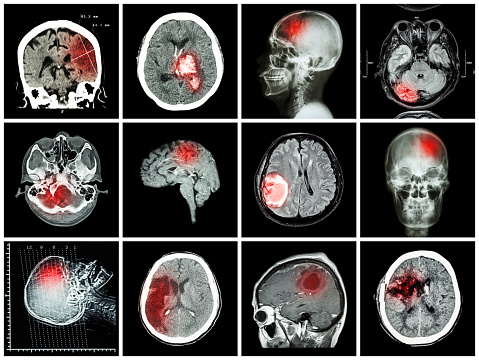

Lacunar infarct is a type of stroke that occurs when one of the arteries supplying blood to the brain gets blocked. These arteries are quite small, which makes them vulnerable to damage. While most arteries in the body gradually become smaller, the arteries of the lacunar stroke branch off a large high-pressure artery. Lacunar stroke ...click here to read more